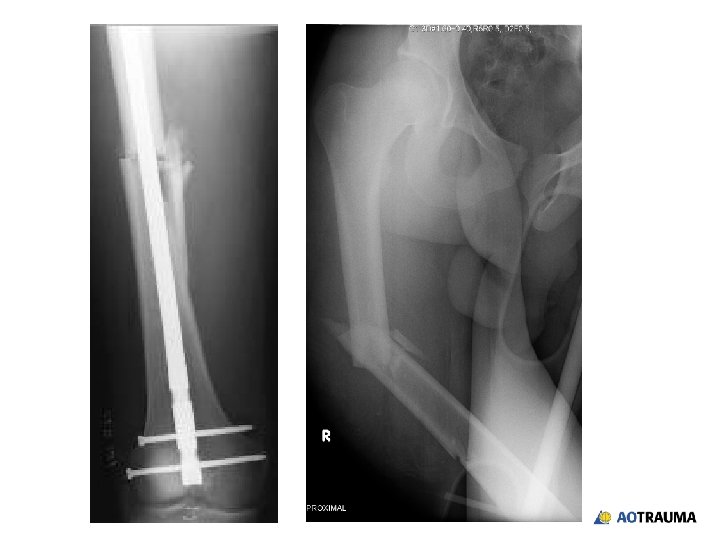

Same patient: 19 -year-old in a motorcycle accident • • • Injury to right

Same patient: 19 -year-old in a motorcycle accident • • • Injury to right femur Closed Neurovascular structures intact Stable vital signs Mid-shaft femoral fracture on left side • Very short and obese

Your treatment of choice is: 1. Piriformis entry, antegrade nail 2. Trochanteric entry, antegrade

Your treatment of choice is: 1. Piriformis entry, antegrade nail 2. Trochanteric entry, antegrade nail 3. Retrograde nail 4. Plate

Same patient: 19 -year-old in a motorcycle accident • • Injury to right femur

Same patient: 19 -year-old in a motorcycle accident • • Injury to right femur Closed Neurovascular structure intact Stable vital signs Mid-shaft femoral fracture on left side Very short and obese Mid-shaft tibial fracture on right side • Patella fracture on right side